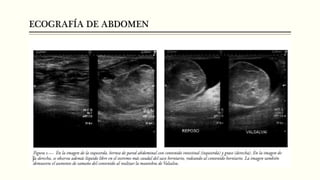

ECOGRAFÍA DE ABDOMEN